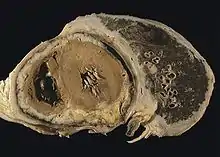

Diffuse pleural mesothelioma with extensive involvement of the pericardium.

Systemic

The mesothelium consists of a single layer of flattened to cuboidal cells forming the epithelial lining of the serous cavities of the body including the peritoneal, pericardial and pleural cavities.[51] Deposition of asbestos fibers in the parenchyma of the lung may result in the penetration of the visceral pleura from where the fiber can then be carried to the pleural surface, thus leading to the development of malignant mesothelial plaques. The processes leading to the development of peritoneal mesothelioma remain unresolved, although it has been proposed that asbestos fibers from the lung are transported to the abdomen and associated organs via the lymphatic system.[52] Additionally, asbestos fibers may be deposited in the gut after ingestion of sputum contaminated with asbestos fibers.